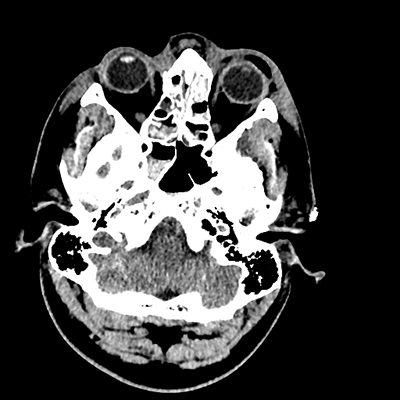

On day 5 of admission, he begins having intracranial hypertension again, spiking up to 40mmHg. You bolus with propofol and fentanyl, to no avail. You then push 30mL of 23.4% NaCl, which provides some brief improvement, allowing you to quickly get a non-contrast head CT. Unfortunately, he's now back up to 36mmHg. You review his labs, and note the following: Na 150, K 3.8, Cl 119, HCO3 18, BUN 21, Cr 0.85, glucose 136, sOsm 320.

NCHCT

NCHCT 1/20 1/20

NCHCT 2/20 2/20